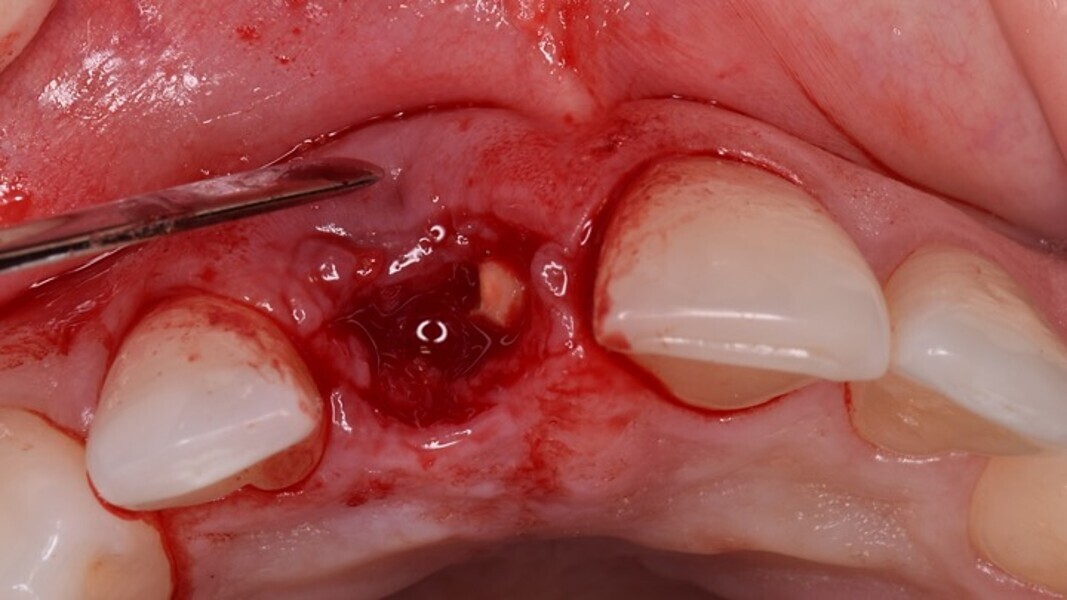

Figura 1. Atrofia de más del 50% de la pared vestibular en el diente 11 con infecciones de repetición de varios años de evolución.